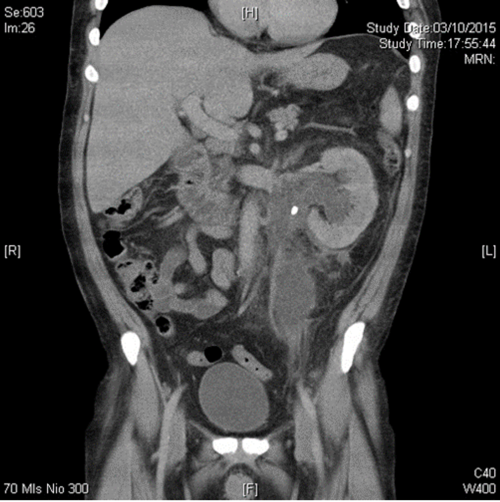

Case 3

A 42-year-old woman presented with left loin pain radiating to the left iliac fossa, pyrexia and feeling generally unwell with spontaneous decompression of the pelvicalyceal system. Her inflammatory markers (WBC, CRP) and serum creatine were raised and she looked unwell.

- What would be your approach to decompress this?

- Name two major complications associated with the percutaneous approach.

The drainage of acute renal obstruction, especially when suspected to be associated with infection, is a urological emergency. Obstruction can be drained by either retrograde ureteric stent (RUS) insertion or percutaneous nephrostomy (PCN). Current guidelines do not provide specific recommendations on the choice between these options [3,4]. This particular patient had a retrograde stent inserted followed by a percutaneous drain in the retroperitoneal collection with broad spectrum antibiotic cover.

-

Quality improvement guidelines for percutaneous nephrostomy recommend a major complication rate of <4% which is achievable [5] although most series report combined major and minor complication rates of approximately 10% [4]; these include severe bleeding, renal loss and septic shock. Reference 5 provides a usefully detailed overview on the subject.